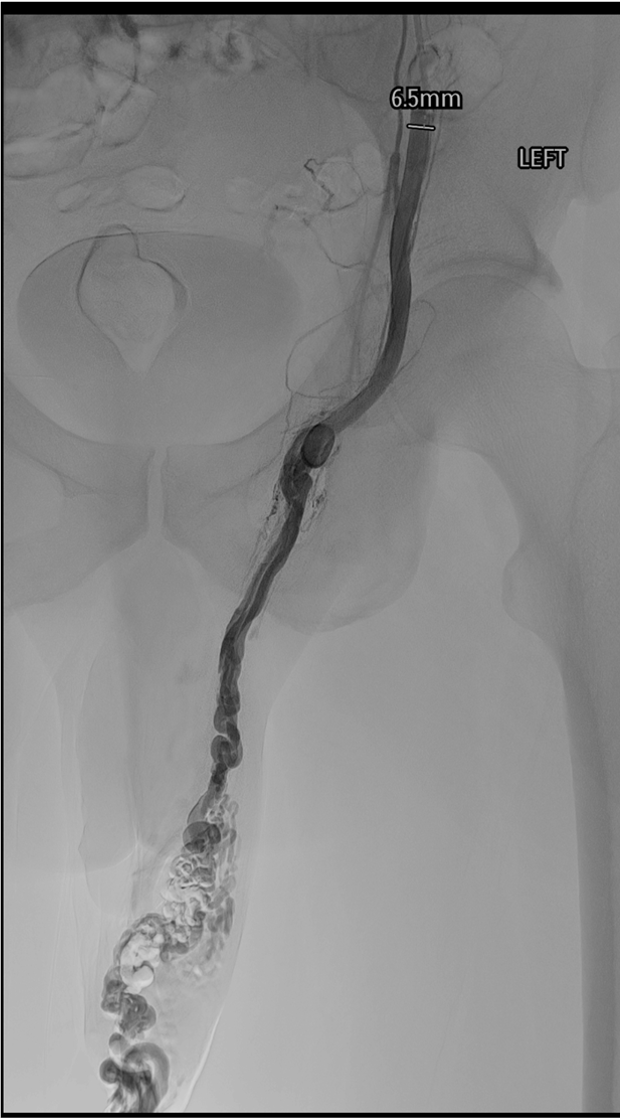

Gonadal vein venogram pre-embolization — dilated internal spermatic vein with contrast filling of the pampiniform plexus confirming reflux.

Gonadal vein catheterization: advance microcatheter through guiding catheter into the gonadal vein; perform diagnostic venogram with Valsalva to confirm reflux and map collaterals (periureteric, capsular renal, cross-pelvic).

Distal embolization first: advance microcatheter to near the inguinal canal (just above the internal ring); deploy coils, plug, or inject STS foam to occlude the distal gonadal vein and pampiniform plexus inflow.

Collateral occlusion: identify and embolize parallel channels (periureteric, retroperitoneal); skipping these is the leading cause of recurrence.

Proximal coil anchor: deploy coils in the proximal gonadal vein near (but not at) the renal vein ostium to prevent coil migration into the renal vein or IVC.

Completion venogram: confirm stasis, no residual reflux on Valsalva, and no non-target filling.